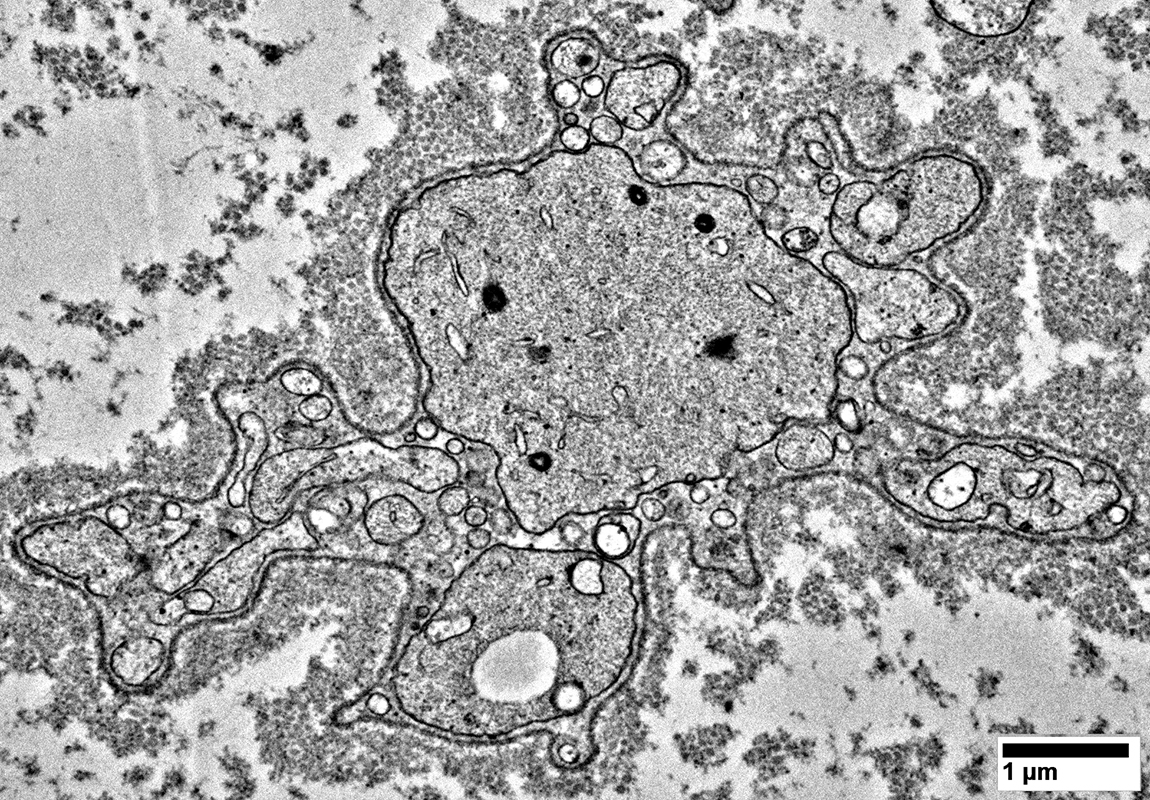

Axons surronded by multiple small Schwann cell processes

From: R Schmidt